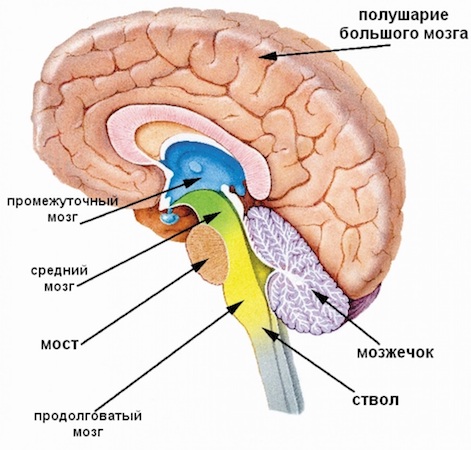

1) Ретикулярная формация – это сложная сеть нейронов, расположенная в центральной части ствола мозга (довольно маленькая по сравнению с большими полушариями или мозжечком). Считается одной из наиболее древних его частей, так как появилась на ранних этапах эволюции мозга. Критически важна в регуляции основных жизненно важных функций, таких как дыхание, сердцебиение, поддержание состояния бодрствования и перехода между сном и бодрствованием. Действует как фильтр для сенсорных сигналов, препятствуя перегрузке мозга информацией и может регулировать передачу болевых сигналов к мозгу.

2) Лимбическая система – также является одной из самых старых частей мозга, хотя и более «новая» по сравнению с ретикулярной формацией с точки зрения эволюционной истории, так как связана с более сложными социальными взаимодействиями и когнитивными способностями. Тоже занимает небольшую часть общего объема мозга. Хорошо развита у млекопитающих, где она участвует в процессах обучения, памяти и эмоционального поведения. Напрямую влияет на такие черты личности, как эмоциональная стабильность, реакция на стресс и взаимоотношения с другими людьми. Помогает усиливать воспоминания на основе эмоциональной значимости, регулирует гормоны, которые влияют на настроение и эмоции, играет ключевую роль в формировании новых воспоминаний и обучения, важна для пространственной памяти и переноса информации в долговременную память.

6) Мозжечок – составляет около 10% от объема головного мозга, но содержит более 50% всех нейронов из-за его плотно упакованной структуры. Традиционно считается, что мозжечок участвует в координации движений, однако недавние исследования показывают, что он также может влиять на когнитивные функции и эмоциональную регуляцию, формирование процедурной памяти, такой как навыки и привычки (совместно с базальными ганглиями).